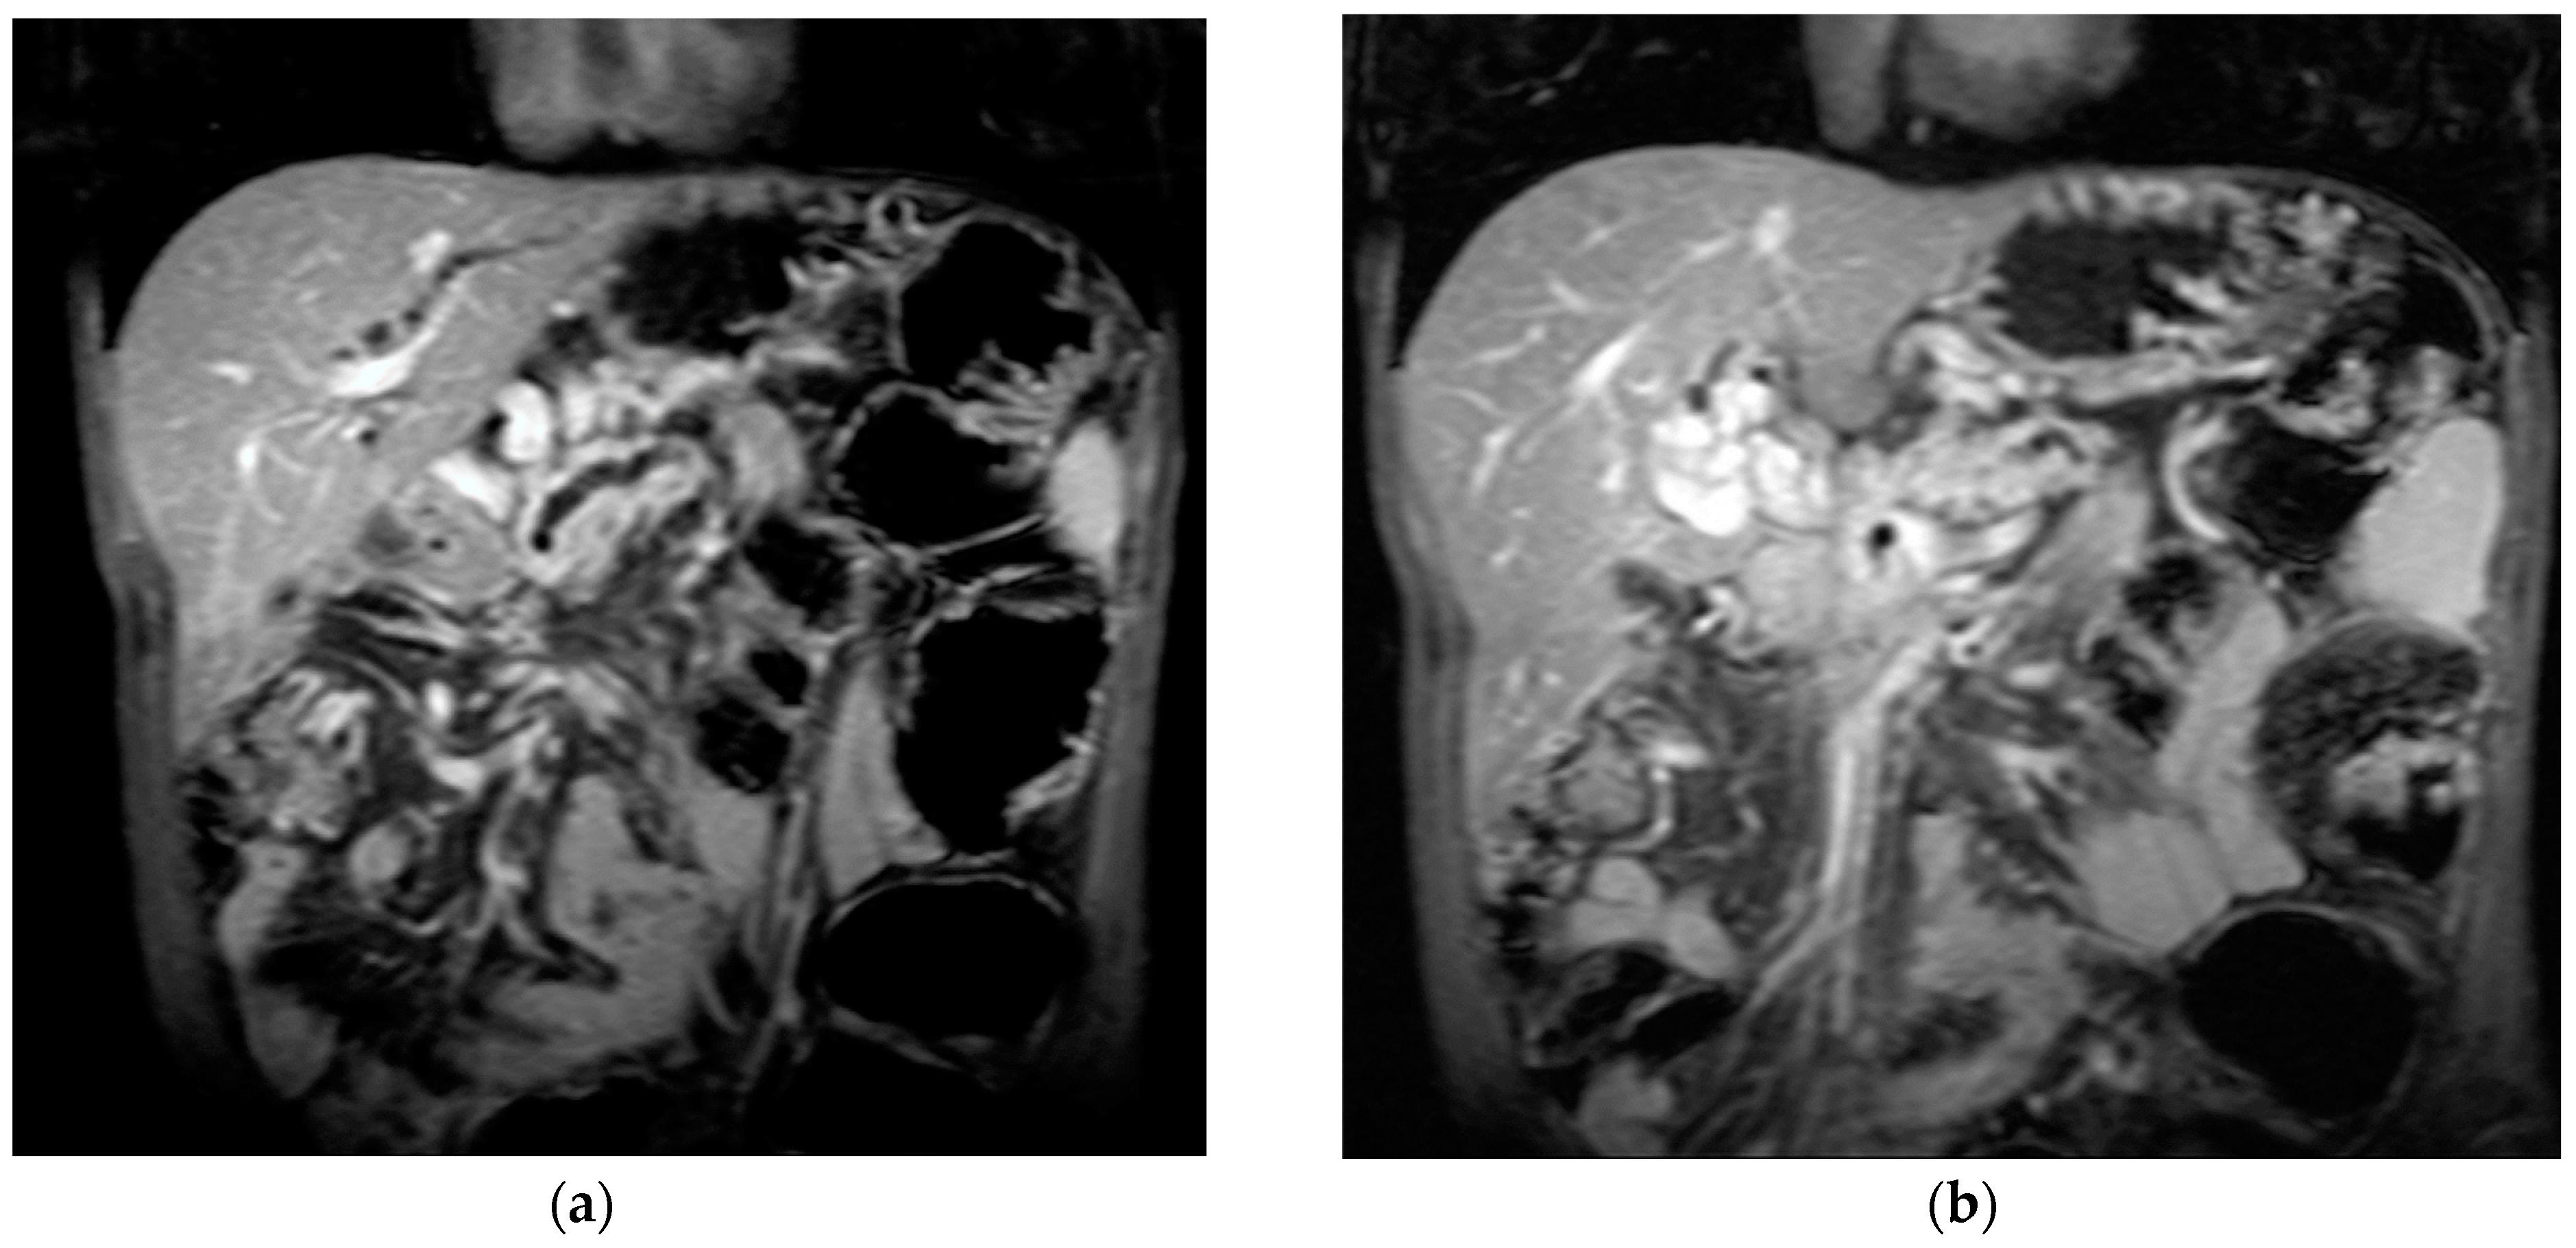

The diagnosis of PVT and PC is made by imaging procedures (transabdominal ultrasound with a Doppler or contrast-enhancing computed tomography scan, magnetic resonance imaging, or angiography in the case of therapeutic intended procedures) [1,3,12,13,14,21,29]. Transabdominal ultrasound is a reliable procedure in 60–100% of cases, with an anechoic aspect in recent cases (requiring Doppler examination or CEUS) and a hypoechoic or hyperechoic aspect in chronic cases [22,29]. Doppler examination may show an anechoic or hypoechoic thrombus and a slower (<15 cm/sec) or absent portal blood flow, and is considered the gold standard (color Doppler) for the diagnosis of PC [1], with a sensitivity and specificity of 95% (Figure 1 and Figure 2) [22]. CEUS can help the diagnosis of benign or malignant PVT, can characterize associated focal liver lesions [30], allows a better characterization of PVT [31], and also permits better detection of PC—Figure 3 and Figure 4 [32]. CT scan and MRI (Figure 5 and Figure 6) are more accurate for the evaluation of liver causes (HCC, abscesses, and other tumors) or other local causes (pancreatitis, diverticulitis, and appendicitis), and for complications (bowel infarction or perforation), and may show permeability of the portal venous system and the flow direction [1,22]. Malignant PVT has intra-thrombus arterial signals on CT, MRI, and/or CEUS, with portal vein diameter frequently 23 mm or above, and with the presence of the tumor at imaging examination (Figure 4 and Figure 6) [21].

Figure 4.

MRI scan in a patient with pancreatic carcinoma. (a) Enlarged portal vein, with intraluminal thrombus. (b) A hilar 5.1/3.3 cm portal cavernoma.

Transabdominal ultrasound with Doppler protocol (Figure 1a,b and Figure 2a,b), CT scan (Figure 3a,b), and MRI (Figure 4a,b) were used for the diagnosis in 88.9, 75.1, and 15% of cases, respectively. CEUS was used for the diagnosis in 49 cases (25.9%) but in only 29 cases was it used for the evaluation of the thrombus, and in two cases for cavernoma diagnosis (Figure 5a,b and Figure 6a,b).